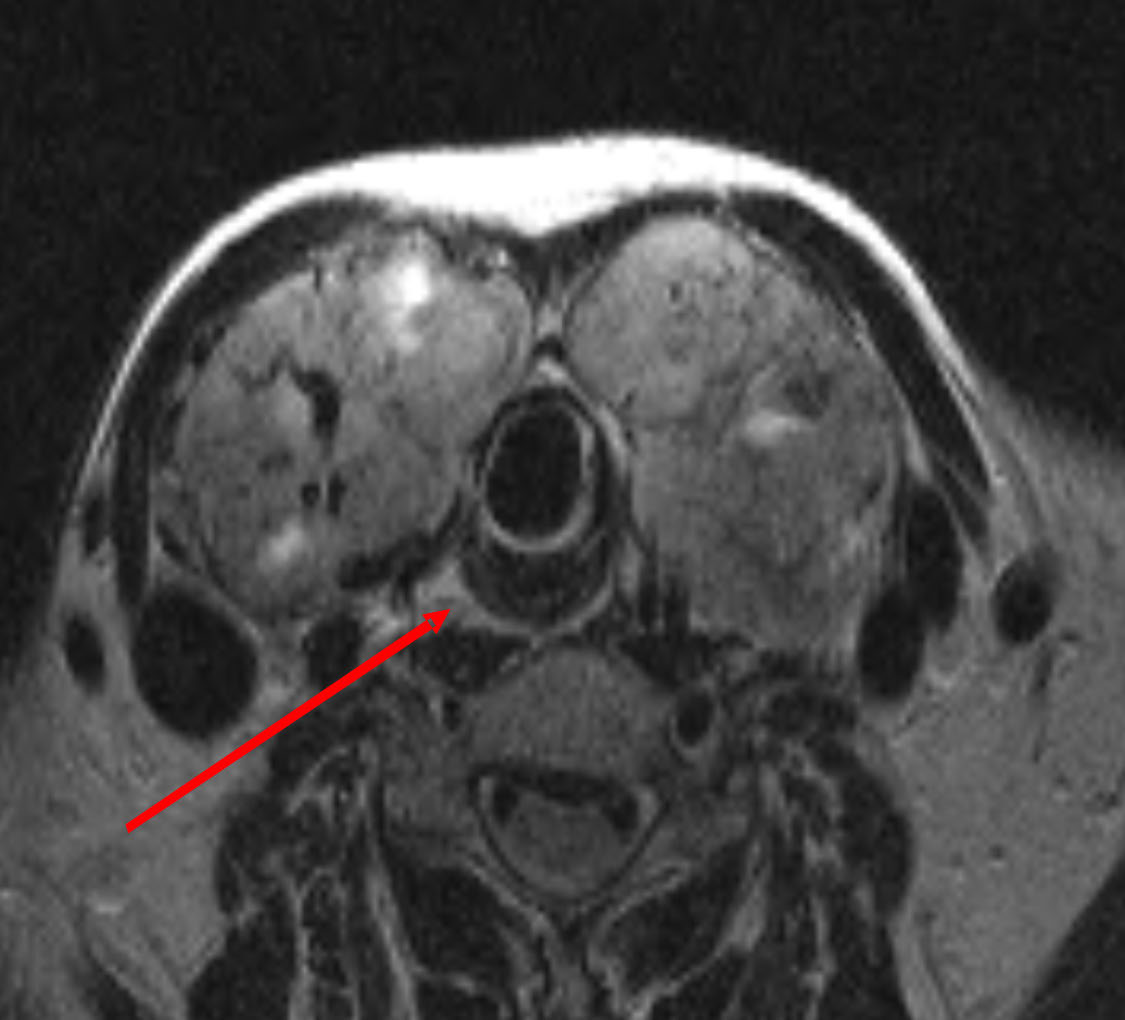

При изучении дооперационных магнитно-резонансных томограмм мягких тканей шеи топография шейного отдела пищевода соответствовала классическим представлениям о хирургической анатомии органа. Несмотря на значительный объем щитовидной железы, смещения и сдавления пищевода не обнаружено (рис. 1).

Рис. 1. Пациент К., 44 года. Диагноз: многоузловой коллоидный зоб, эутиреоз. Объем щитовидной железы 173 см3. Смещение и сдавление пищевода отсутствует